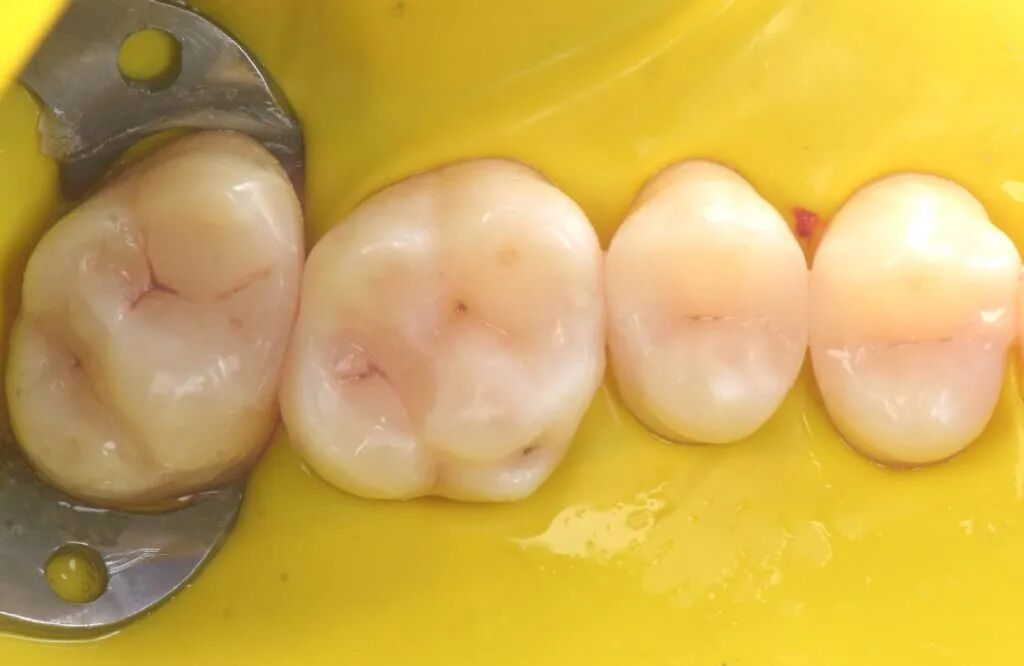

图1. 一位患者主诉左上后牙食物嵌塞咬合不适。左上象限(从第一前磨牙至第二磨牙)龋病情况如图。

图3. 局部麻醉,橡皮障隔离,清理牙齿。